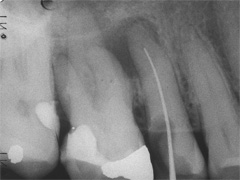

An Zahn 17 hatte sich, vom Patienten unbemerkt, eine Fistel manifestiert. Anlass für eine Übersichtsaufnahme, welche neben 2 gefüllten auch einen ungefüllten Wurzelkanal offenbarte (Bild 1). Der Verursacher der fistelerhaltenden Eiterproduktion war damit identifiziert. Um diesen Prozess zu unterbrechen, wurde in gleicher Sitzung ein Zugang angelegt, der Kanal vermessen, gereinigt, mit Einlage versehen und wieder verschlossen.

Die Behandlung fühlte sich gut an, so war die Fistel geschlossen nach 3 Wochen, als die Wurzel gefüllt wurde. Und dieses gelang trotz Haken-Wurzel fast perfekt (Bild2). Der Patient kam 8 Monate später wieder auf uns zu und bat, um Überbrückung der Lücke davor. Gross geriet das Staunen dann, die Fistel griente uns schon von Weitem an.

Zu tiefst beleidigt gab's hinten-aussen 2 neue Einlagen vor Wiederbefüllung. Und später, um die Brückenkonstruktion nicht zu gefährden, wurden im Anschluss an die Abformung kassenfreundlich, bei bestehender Anästhesie, beide äusseren Wurzeln ihrer Spitzen beraubt. (Bild 3).

Behandlungsspanne ca. 10 Monate